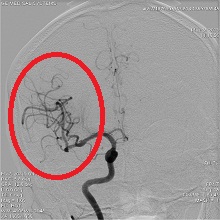

![]() 中大脳動脈閉塞

血栓除去術後(血流再開後)

急性の心筋梗塞・くも膜下出血・脳梗塞・動脈出血などに対応するアンギオ装置です。

24時間いつでも対応しております。